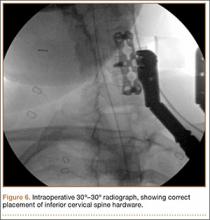

Intraoperative lateral fluoroscopy was obtained to confirm the C5-C6 and C6-C7 level prior to discectomy. The musculature of the patient’s neck and shoulder made visualization of the C6-C7 disc space difficult on the lateral radiograph (Figure 5). One attempt was required to obtain the 30º–30º oblique view, which was used to ensure correct placement of the screws and plate (Figure 6).

Postoperatively, the patient’s pain had improved, and radiographs confirmed adequate hardware placement. He was discharged 1 day after surgery (Figure 7). Imaging at the patient’s 6-week follow-up confirmed adequate fusion from C5-C7, stable disc spaces, and anatomically aligned facet joints. His Neck Disability Index was 34/50 preoperatively and 32/50 at 2-week follow-up.